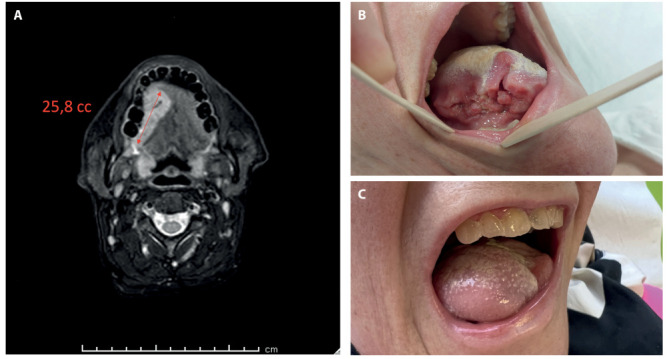

Background and aim: The radial forearm free flap (RFFf) and the antero-lateral thigh flap (ALTf) are considered the "key flaps" for oral cavity reconstruction. Nowadays, the literature lacks of an objective and standardized decision-making algorithm for the flap choice. The aim of this study is to describe a decision-making algorithm concerning the more appropriate flap, RFFf or ALTf, in the reconstruction of intra-oral soft tissues based on the volumetric analysis of the defect with a pre-operative Magnetic Resonance Imaging (MRI), updating our previous surgical experience.

Methods: We conducted a retrospective observational study including 77 patients who underwent microsurgical reconstruction with RFFf or ALTf after tumor resection of the soft tissues in the oral cavity. During follow-up, patients were evaluated using the UW-QOL questionnaire.

Results: Analyzing the scores of the UW-QOL questionnaire based on the size of the tumor on preoperative MRI we found that for tumor volume <50cc and between 50-70cc, the patients reconstructed with RFFfobtained statistically significant better scores compared to the ALTf group, while for tumor volume >70cc, the patients reconstructed with ALTf reported statistically significant better scores.

Conclusions: Pre-operative RMI-guided volumetric assessment of oral cancer plays a key role in the planning of adequate soft tissue reconstruction and can objectively help surgeons in the correct choice of the flap (RFFf vs. ALTf) for each case based on preoperative tumor size, suggesting for defects <50cc and between 50 and 70 cc a reconstruction with RFFf, while for defects >70cc a reconstruction with ALTf.